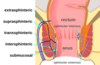

# Abdome: cólon e reto Classificação de Parks das fístulas perianais de acordo com a RM? (4)

1. Interesfincteriana – trajeto entre os esfíncteres interno e externo, o mais comum; 2. Transesfincteriana – atravessa o esfíncter externo em direção à fossa isquiorretal; 3. Supraesfincteriana – sobe acima do esfíncter externo e desce para a fossa isquiorretal; 4. Extraesfincteriana – não passa pelos esfíncteres; vai do reto diretamente à pele perianal; Temos ainda a superficial – trajeto raso, sem envolvimento dos esfíncteres (dd fissuras).